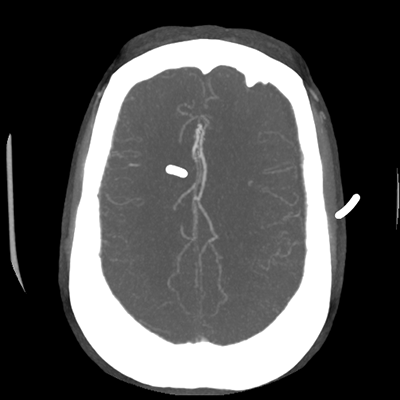

The patient goes down to CT. The following images are obtained. The subdural fluid collection is stable, as is the ventricular caliber.

Starting with the non-contrast head CT, we can appreciate that there's actually not much residual subarachnoid blood at all; it's essentially all resorbed already (and cleared through the EVD). The ventricular caliber is stable. With the CTA head (for convenience's sake, the MIPs were shown), it's subtle, but we can see that the PCAs on each side are not as smooth and regular. The right MCA, starting at the bifurcation, also becomes narrower. This is [radiographic] vasospasm. Now, looking at the CT perfusion-- specifically, the Tmax (MTT) map that were selected-- there's clearly some abnormality within the bilateral cerebellar hemispheres and occipital lobes. Not a lot, but it's there. Delving further into this map, we can appreciate that the areas of abnormality are mainly green, signifying that these areas have Tmax > 6 seconds. This is the threshold that is specific, not sensitive, for vasospasm.

Putting this all together, we have thus identified radiographic vasospasm with the vessel imaging, with perfusion abnormalities that are concordant with it. Does the area of vasospasm and hypoperfusion correlate with the patient's clinical exam?

Yes! It does. The patient had a decline in level of consciousness with diffuse loss of motor function. This does correlate to the basilar territory. (Alternatively, bilateral MCA vasospasm could also be responsible, reminding us that a decline in consciousness could technically be focal/multifocal.) Thus, we can say that this patient does have clinical vasospasm. Whether this will develop into irreversible DCI remains to be seen; at least, the non-contrast head CT and the other portions of the CT perfusion (not shown) currently don't [yet] suggest infarction.